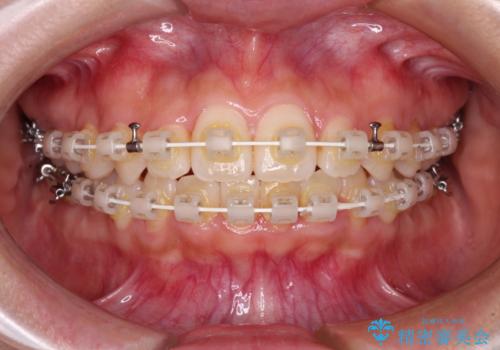

- 矯正装置

- 審美装置

ワイヤー矯正は見た目や装置が当たることでの痛みを気にされる方が多いですが、月1回来院して処置をしてもらうだけで歯並びが整うため、大変お勧めです。